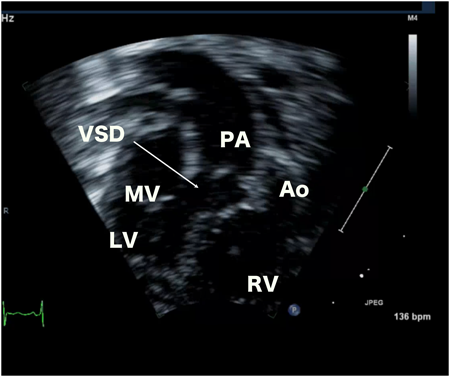

例えば図2では,肋骨下のwindowから心室中隔欠損を描出した両大血管右室起始症の画像である.バイプレーンモードや実際に探触子をその場所で傾けて目標部位:心室中隔欠損と周囲構造物:三尖弁,肺動脈弁,大動脈弁のすべてがよく描出できているのを確認する.さらに2D画像上でfocus,gain,dynamic rangeなどの調整を行う.このとき心室中隔欠損を正面からみた2D画像(en face view)を基本に3D画像をフルボリュームモードで取り込む.このように収集前に2D画像でよく確認することが非常に大切である.

図2 両大血管右室起始症の肋骨下断面像

VSDを中心においてなるべくすべての構造物が鮮明に描出されているwindowをみつけ,収集の基本windowとする.VSD: 心室中隔欠損,RV: 右室,LV: 左室,MV: 僧帽弁,PA: 肺動脈弁,Ao: 大動脈弁